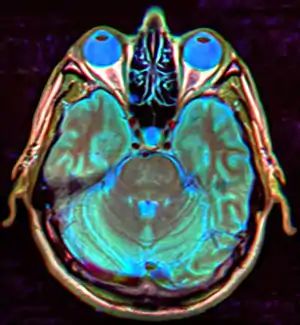

![]() | |

| MRI of Empty Sella | |